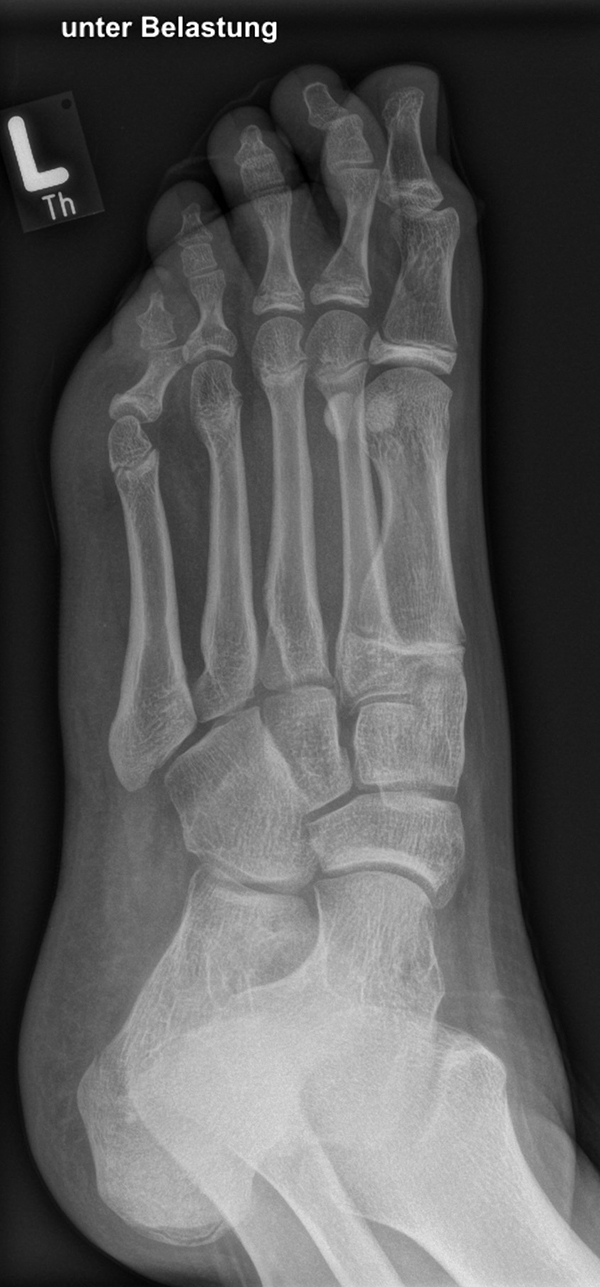

In der Regel bestehen aktive Wachstumsfugen bei Mädchen bis zum 12. und bei Jungen bis zum 14. Lebensjahr, mit Abweichungen von einem Jahr nach unten und nach oben. Präzise Informationen unter anderem darüber gibt das präoperative Röntgenbild (Abb. 2).

Abb. 2 a-c: offene Wachstumsfugen MT I Basis und Zehen (a), teilweise geöffnete Wachstumsfugen (b) und geschlossene Wachstumsfugen (c).